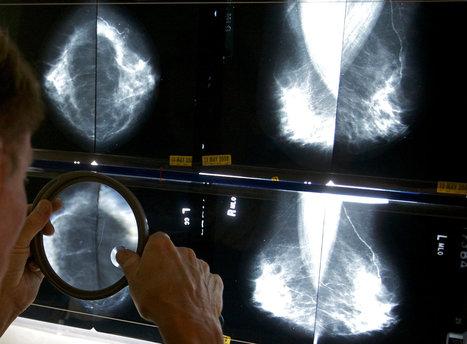

The recommendations, from a working group of the National Cancer Institute, were published on Monday in The Journal of the American Medical Association. They say, for instance, that some premalignant conditions, like one that affects the breast called ductal carcinoma in situ, which many doctors agree is not cancer, should be renamed to exclude theword carcinoma so that patients are less frightened and less likely to seek what may be unneeded and potentially harmful treatments that can include the surgical removal of the breast.